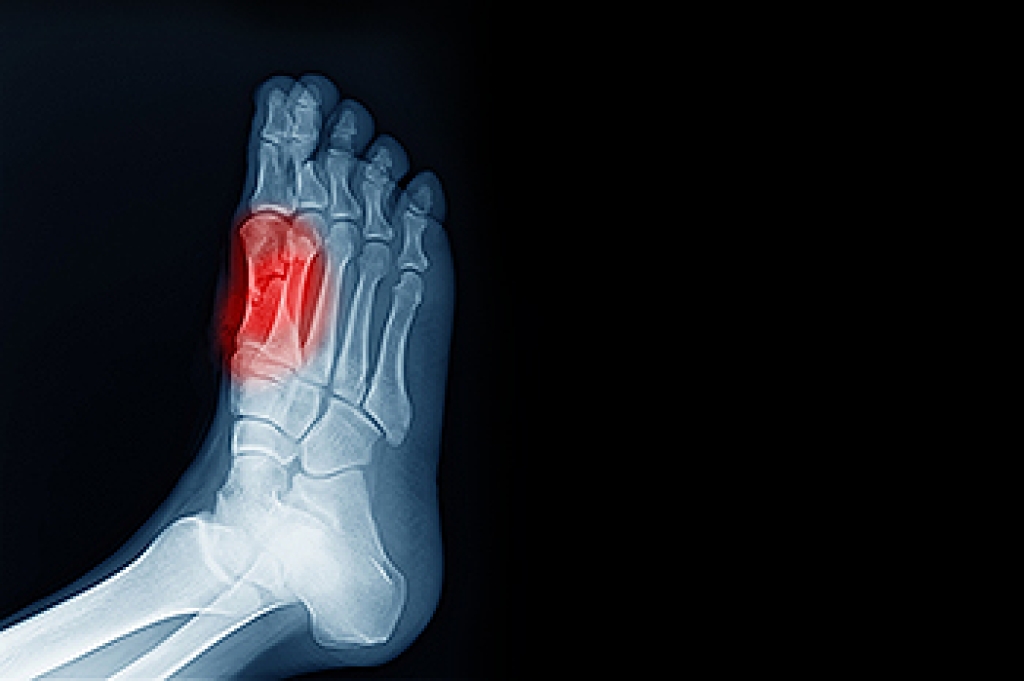

In many cases the cause of toe pain is obvious, but in others, a podiatrist may want to use more advanced methods to determine the problem. These can range from simple visual inspections and sensation tests to X-rays and MRI scans. Prior medical history, family medical history, and any recent physical traumatic events will all be taken into consideration for a proper diagnosis.

- Fractures (broken bones)

Treatments for toe pain and injuries vary and may include shoe inserts, padding, taping, medicines, injections, and in some cases, surgery. If you believe that you have broken a toe, please see a podiatrist as soon as possible.